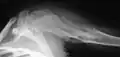

Enchondromas localized in the upper part of the humerus of the same patient